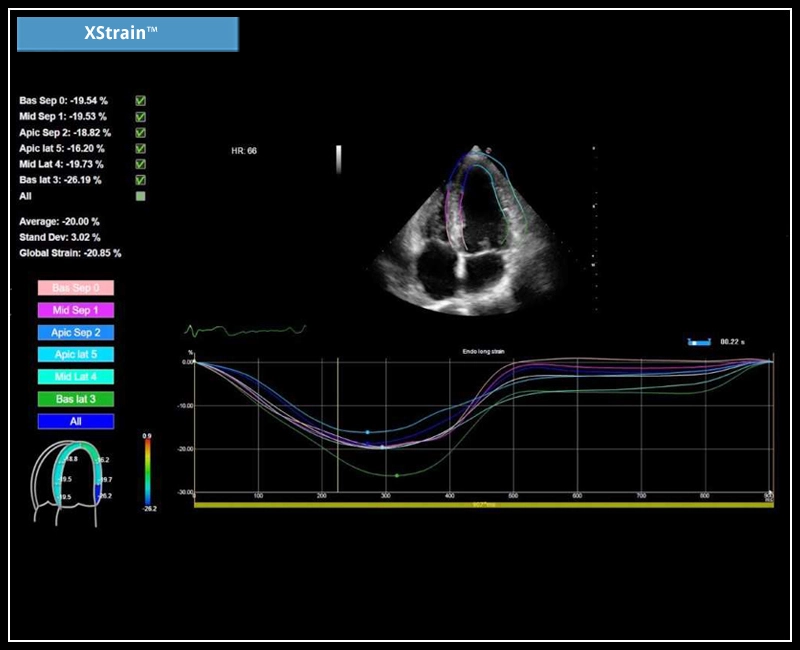

MyLab™X5 - XStrain

MyLab™X5 - XStrain